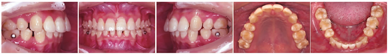

颌面部检查:面部左右基本对称,颏部略右偏,微笑时口角对称,牙列中线与面中线一致,上下唇前突,鼻唇角偏小,颏部发育可(图1)。

像口内检查:恒牙列18~27、37~47。上下中线基本对齐。上下前牙拥挤,尖牙及磨牙中性关系。牙体及牙周未见明显异常(图1)。